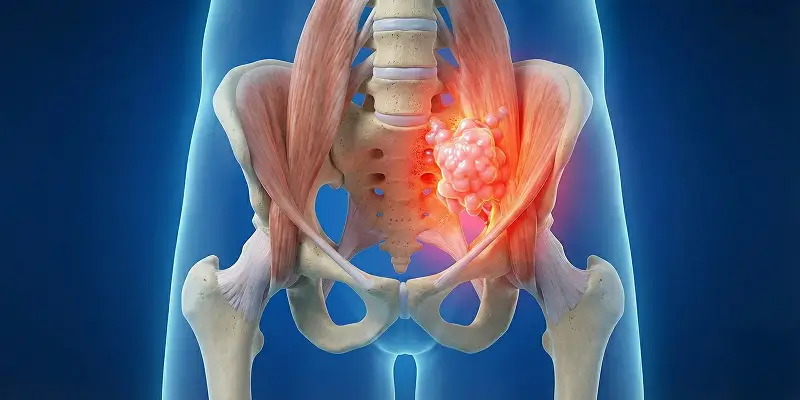

Kemik metastazı, başka organlardan kemiğe yayılan kanserin neden olduğu ciddi bir durumdur. Belirtileri, teşhisi, tedavi yöntemleri ve ağrı yönetimi.

Yumuşak doku sarkomu, kas, yağ, bağ dokusu, sinir ve damar yapılarından köken alan kötü huylu tümörlerdir. Belirtileri, nedenleri, teşhisi ve tedavi yöntemleri.

Dev hücreli kemik tümörü, osteoklastik dev hücrelerin kontrolsüz çoğalmasıyla oluşan agresif bir kemik tümörüdür. Belirtileri, tanı yöntemleri ve tedavi seçenekleri.